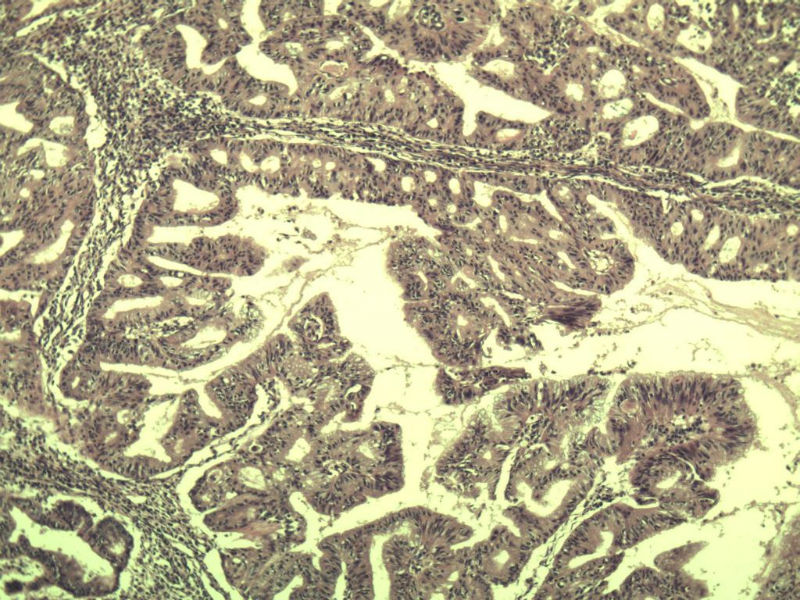

名称:图2

描述:a145.Jpg.jpg